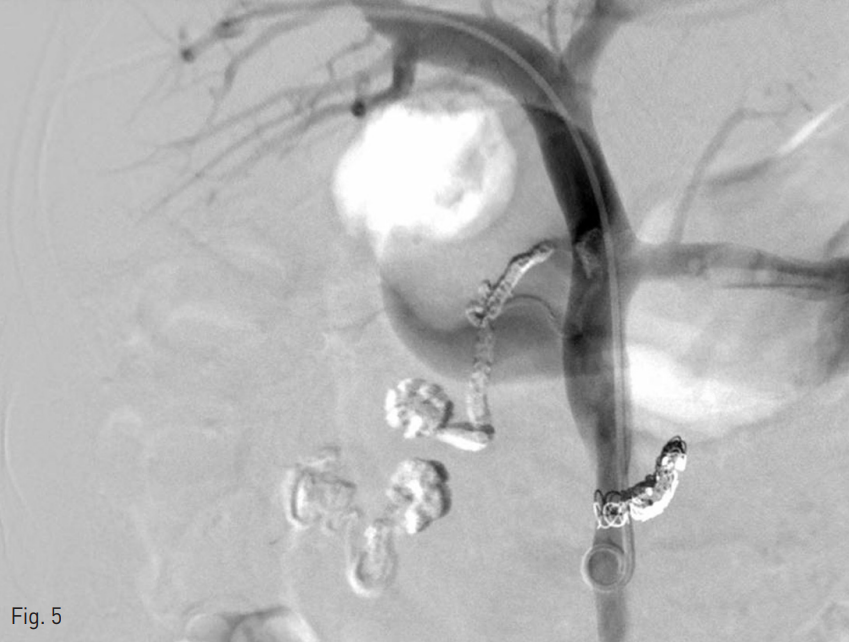

시술 후 시행한 간문맥조영술 상에서 십이지장 정맥류로의 혈류가 관찰되지 않았다 (Fig. 5). 이에 경피적 문맥 천자 경로에 대하여 glue와 lipiodol 혼합물을 통한 색전 후 시술을 종료하였다.

Fig. 5

After embolization for duodenal varices, follow up portogram shows non-visualization of ectopic varices with patent portal vein flow.